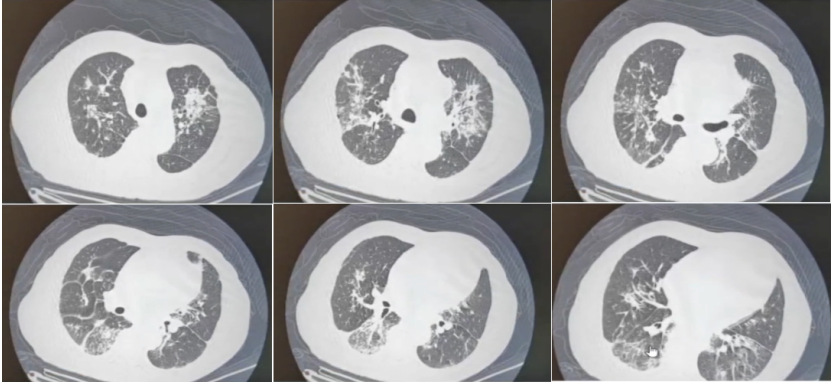

8月19日复查胸部CT可见双肺空洞样改变和下肺渗出性病变较前缓慢吸收(6)9月5日胸部CT发现肺部病变较前进一步吸收(7)9月12日(出院前)胸部CT可见病变吸收更明显(8)。患者除偶尔发热,整体情况较好。

图片

6  复查胸部CT(2022-08-19)

7  复查胸部CT(2022-09-05)

8  复查胸部CT(2022-09-12)

2023年9月20日复查胸部CT示肺部病灶基本吸收,仅残留纤维条索影(图12)。停用抗真菌药,后续患者状态良好。

12  随访胸部CT(2023-09-20)